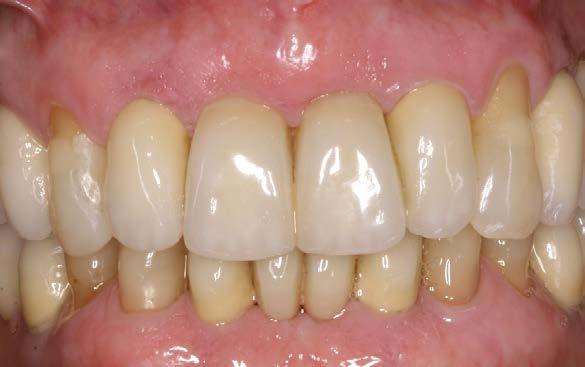

caninos y premolares mediante tratamiento periodontal intensivo. Esta decisión favoreció la integración funcional de dientes e implantes, manteniendo la propiocepción y mejorando el control de posibles sobrecargas funcionales como el bruxismo.22-24

La paciente continúa en seguimiento. A los 8 años, la estabilidad de los tejidos duros y blandos, así como la estética de la rehabilitación, era completa (Figura 9-11). A los 12 años se observó

una buena progresión del tratamiento, sin cambios reseñables (Figura 1214). A los 20 años de seguimiento se constató una evolución estable, sin pérdida ósea en dientes ni implantes, y con buena salud de los tejidos periimplantarios (Figura 15-17).

observaron diferencias clínicas significativas entre estas configuraciones en cuanto a pérdida ósea o comportamiento tisular, lo cual se ve claramente reflejado en este caso clínico con seguimiento a largo plazo.19-21

Figuras 15-16. Imágenes intraorales a los 20 años de seguimiento.

Figura 17. Radiografía final que evidencia la estabilidad completa de los tratamientos a los 20 años.

Implantes y propiocepción: la importancia de preservar dientes clave en pacientes con enfermedad periodontal avanzada